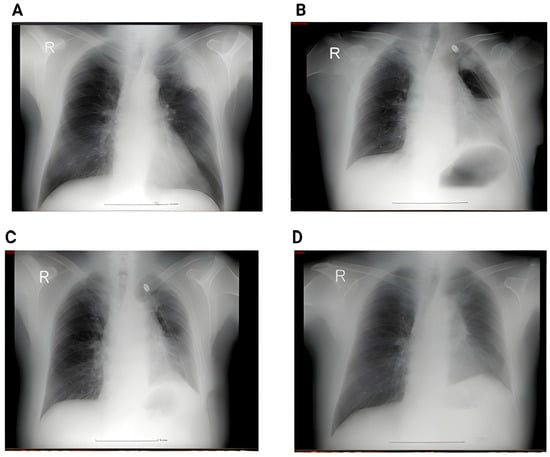

Figure 1 below shows the imagistic changes on x-ray following surgery.

Figure 1. (A) Preoperative chest X-ray showing a pulmonary nodule projected in the middle lobe. No pleural effusion or pulmonary infiltrate. (B) Second postoperative day showing small bilateral pleural effusion, accentuation of the interstitial markings, and a small infiltrate in the right lower lobe; (R = right).

Figure 2. (A) Perioperative RX showing a left superior lobe nodule. No pleural effusion, no atelectasis. (B) Second day postoperative x-ray showing hydropneumothorax with significant fluid in the left pleural cavity, and passive atelectasis. (C) 3rd day postoperative showing effective drainage of the fluid with re-expansion infiltrates and juxta-phrenic peak sign. (D) 6 weeks postoperative showing no pleural effusion, no infiltrates.